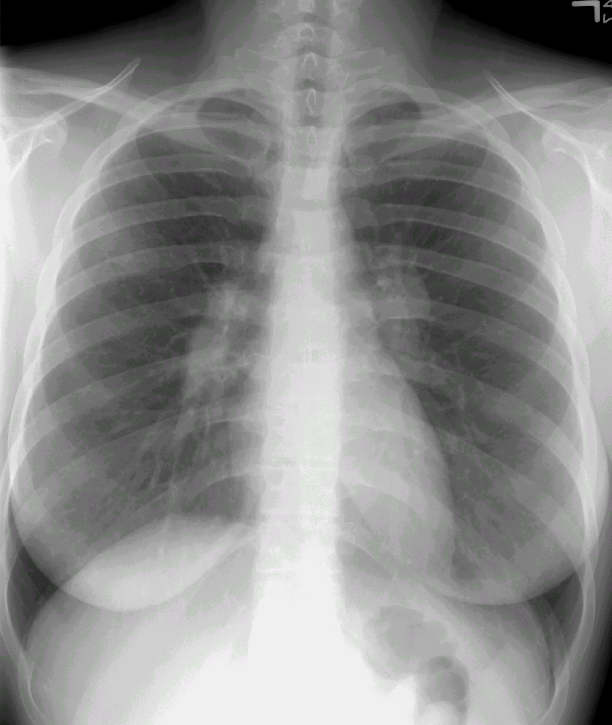

Scott WilliamsAutoimmuneAutoimmune > Sarcoid > Images > Sarcoid1AApril 2, 2002CardiacCardiac > Congenital > TetApril 2, 2002AutoimmuneAutoimmune > AnkspondylitisApril 2, 2002AutoimmuneAutoimmune > ProteinosisApril 2, 2002Infections-InflammatoryInfect > Fungus > Blasto > Images > Case1April 2, 2002Infections-InflammatoryInfect > BacterialApril 2, 2002Mediastinal MassesMediastinum > NeuroblastomaApril 2, 2002PETPET > PET tumor imaging > Thyroid CancerApril 2, 2002CardiacCardiac > Adultdz > CACalcApril 2, 2002CardiacCardiac > Adultdz > Rheumatic > ImagesApril 2, 2002Previous PagePage 96 of 265Next PageTop StoriesCTNew benchmark helps monitor cumulative CT radiation doseThe findings highlight the need for systematic dose tracking and rigorous justification of imaging.Radiation Oncology/TherapyStudy questions routine use of radiotherapy after bone surgeryUltrasoundCEUS outshines color Doppler imaging for indeterminate kidney lesionsWomens ImagingWomen's Imaging MinnieCast, Episode 2: Risk-based vs. annual mammography screening, part 1Digital X-RayChest x-rays reveal atherosclerosis in patients undergoing amputations